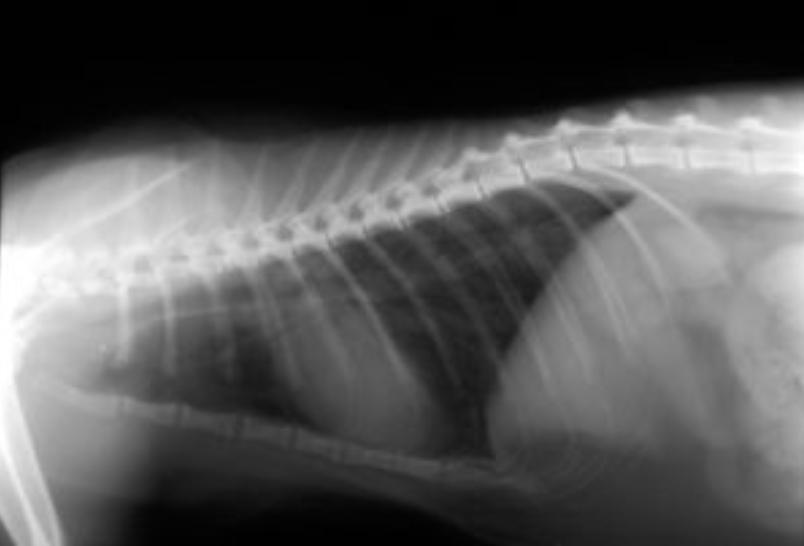

经PCR诊断为继发性支原体感染的哮喘猫的x光片,左侧肺部有斑片状阴影

图片来源:参考文献

下呼吸道感染 的症状包括咳嗽、嗜睡、厌食、呼吸急促或呼吸困难、流鼻涕和发热。如果猫出现 呼吸困难或呼吸急促 应考虑下呼吸道感染。